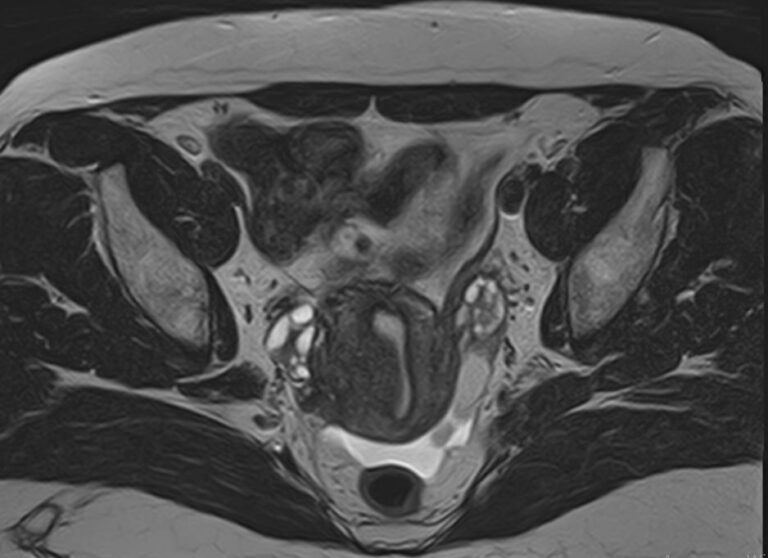

В клинике «Доступная медицина» МРТ яичников выполняется на современном томографе экспертного класса TOSHIBA VANTAGE TITAN 1,5 Тесла, который производит послойное сканирование анатомической области яичников в трех различных плоскостях с последующей цифровой обработкой полученных данных и построением трехмерных изображений исследуемой зоны.

Стандартная МРТ яичников без контрастирования дает детальную информацию о состоянии яичников и окружающих тканей, но при необходимости уточнения патологических изменений, при проведении дифференциальной диагностики, внутривенно вводится контрастное вещество.

Что показывает МРТ яичников?

На МР-исследовании могут быть обнаружены:

• пороки развития;

• снижение числа фолликулов или их отсутствие;

• функциональность имеющихся фолликулов;

• кисты;

• острое и хроническое воспаление, абсцессы;

• опухолевые процессы.